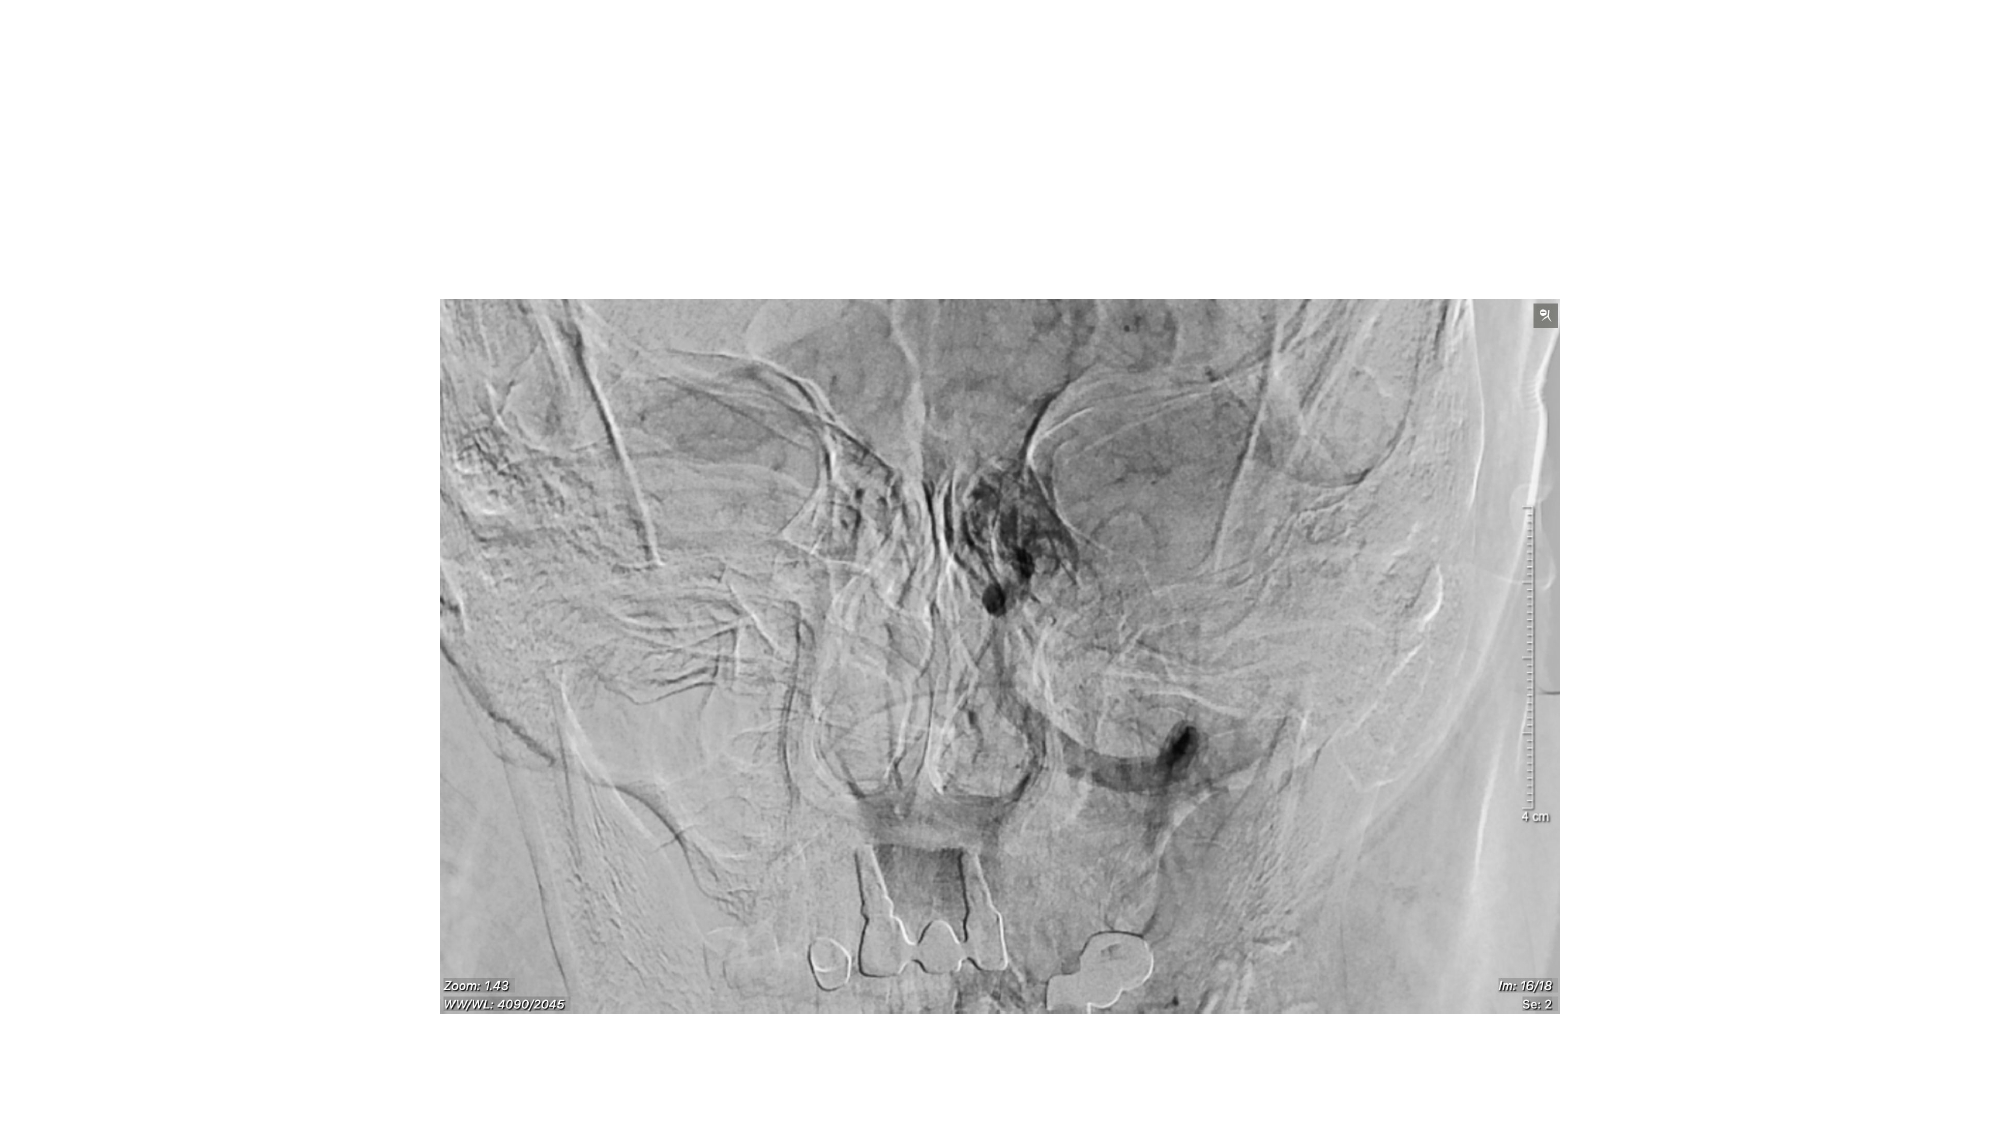

| 13:30 - 14:10 | Surgical management of skull base trauma Endovascular Management of Post-Traumatic Intracranial Vascular Lesions | Assoc. Prof. Nguyen Trong Yen Dr. Nguyen Ngoc Cuong | |

| 15:10 - 16:10 | Interactive Case Demonstration and Discussion II: ~20 minutes each, (5 minutes presentation followed by 15 minutes discussion) Practicals: How I am doing it? Participants present case presentations about how they do it? The faculty comment on and discussion. 1. Endoscopic approach in post-traumatic CSF leakage - Dr. Nguyen Thanh Xuan 2. Endovascular approach in CCF - Assoc. Prof. Le Thanh Dung | Prof. Christian Matula International & local faculties Participants | |